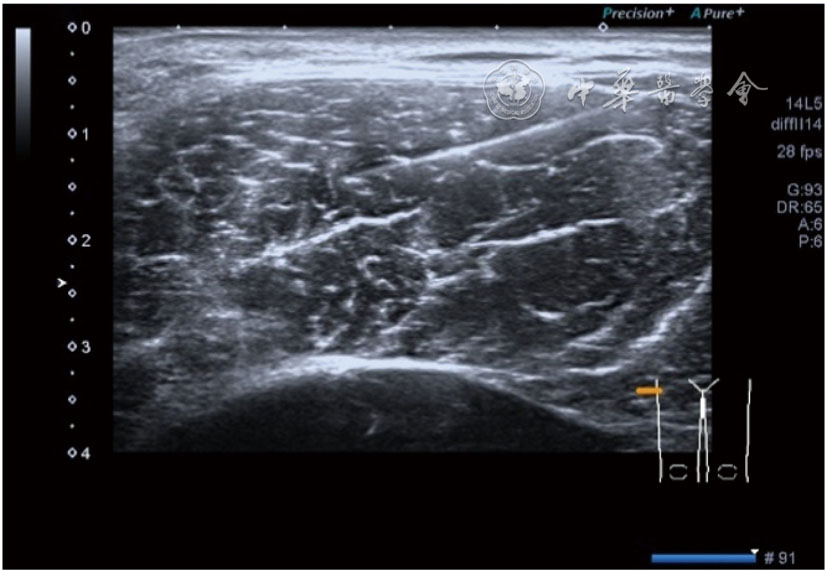

4.腓总神经分支卡压的治疗。常见腓浅神经、腓深神经感觉支卡压。主要表现为足背侧的感觉减退。腓深神经只支配第一、二足趾之间的感觉,腓浅神经支配的感觉区域较多,第一、二足趾之间外的足背感觉均由腓浅神经支配,根据感觉障碍区域确定卡压神经,超声可以明确卡压部位和原因。超声可显示卡压神经增粗,回声减低,局部软组织回声不均匀等(图4445)。治疗以液压松解药物注射为主。以腓深神经为例进行介绍。常见卡压部位在小腿和足背部。根据卡压部位不同,患者采取不同的体位。如果在小腿部采用平卧位,膝关节伸直位即可。穿刺区域常规消毒,探头涂抹耦合剂后套入无菌手套碘伏消毒或使用无菌耦合剂。将探头置于患者皮肤表面,小腿部位采用短轴扫查,确定神经卡压最明显的部位后,用一次性5 ml注射器,应用25G注射针头抽吸0.5%利多卡因4 ml+地塞米松3 mg平面内进针到达神经周围,注意回抽无血液回流后进行注射(图46),完成注射松解,拔出针头,局部压迫3分钟,创可贴覆盖。如果在足背部可以采取平卧位,屈髋、屈膝将足平放于治疗床面。治疗前准备同小腿部,采用长轴显示神经,确定神经卡压最明显的部位后,用一次性5 ml注射器,应用25G注射针头抽吸0.5%利多卡因2 ml+地塞米松1 mg平面内进针到达神经表面进行注射(图47),完成注射松解,拔出针头,局部压迫3分钟,创可贴覆盖。

图46 腓深神经在小腿近端腓深神经、腓浅神经分开处卡压及穿刺注射治疗超声图像